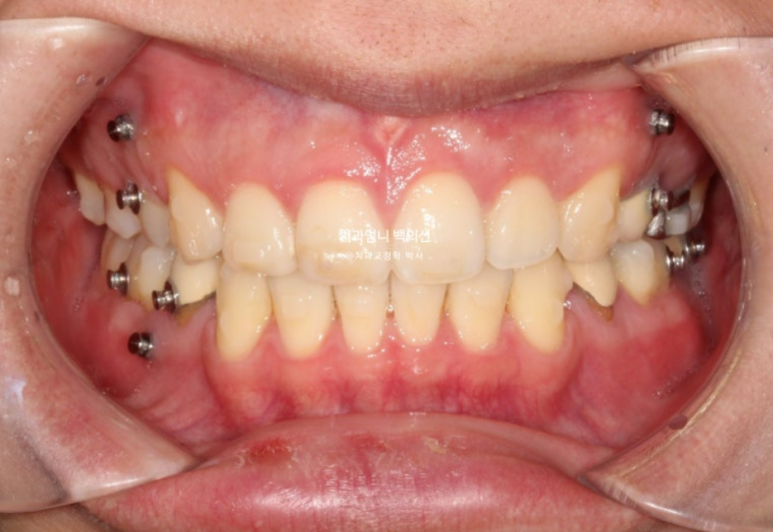

24년 3월까지, 1년 3개월간 70개의 장치를 일주일 간격으로 모두 낀 후 모습입니다.

24.03

중심선은 많이 개선되었으나 여전히 약간의 불일치가 남아있습니다.

1차 세트를 마쳤을 뿐인데도 교합이 좋은편입니다.

앞니 사이 벌어진 틈이 있습니다.

발치공간 1mm가량 남았네요.

이 부분들을 더 개선하고자 재제작에 들어갔습니다.